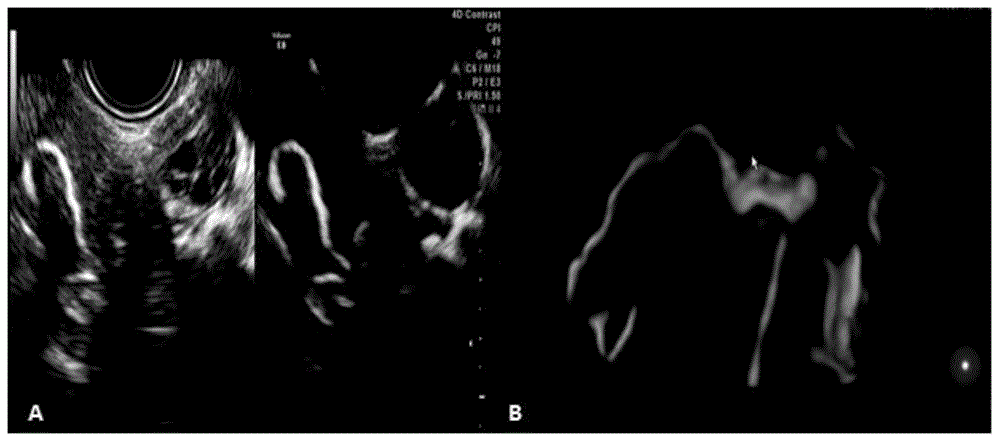

一种输卵管阻塞性不孕的几丁糖丹参混合液及其应用